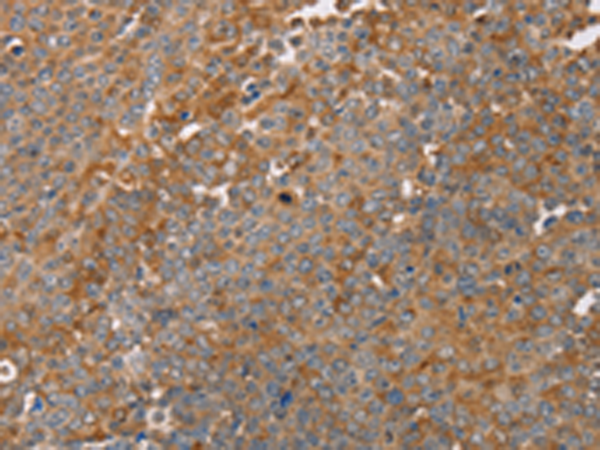

分类: 科研抗体货号: P08296别名: HSCO; YF13H12应用: WB,IHC反应种属: Human, Mouse

分类: 科研抗体货号: P08308别名: DRR1; TU3A应用: IHC反应种属: Human

分类: 科研抗体货号: P08314别名: MLSTD1; SDR10E2应用: WB,IHC反应种属: Human, Mouse